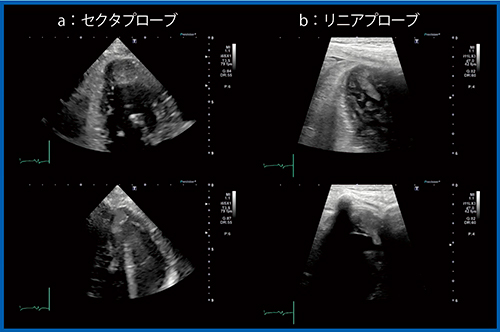

症例3は,70歳代,女性。がん治療関連心筋障害(CTRCD)により,びまん性左室壁運動低下が出現し,心尖部に比較的輝度の高い異常構造物を認めたが,周囲の肉柱様構造物ならびに多重反射の影響で明瞭な画像描出は困難であった(図9 a)。リニアプローブでは心尖部の内腔の状態が明瞭に描出され,可動性心尖部血栓を容易に描出できている(図9 b)。

ライブデモでは,リニアプローブによる心尖部領域の描出のポイントを紹介する。

図9 症例3:セクタおよびリニアプローブによる心尖部の血栓の描出(CTRCD症例)